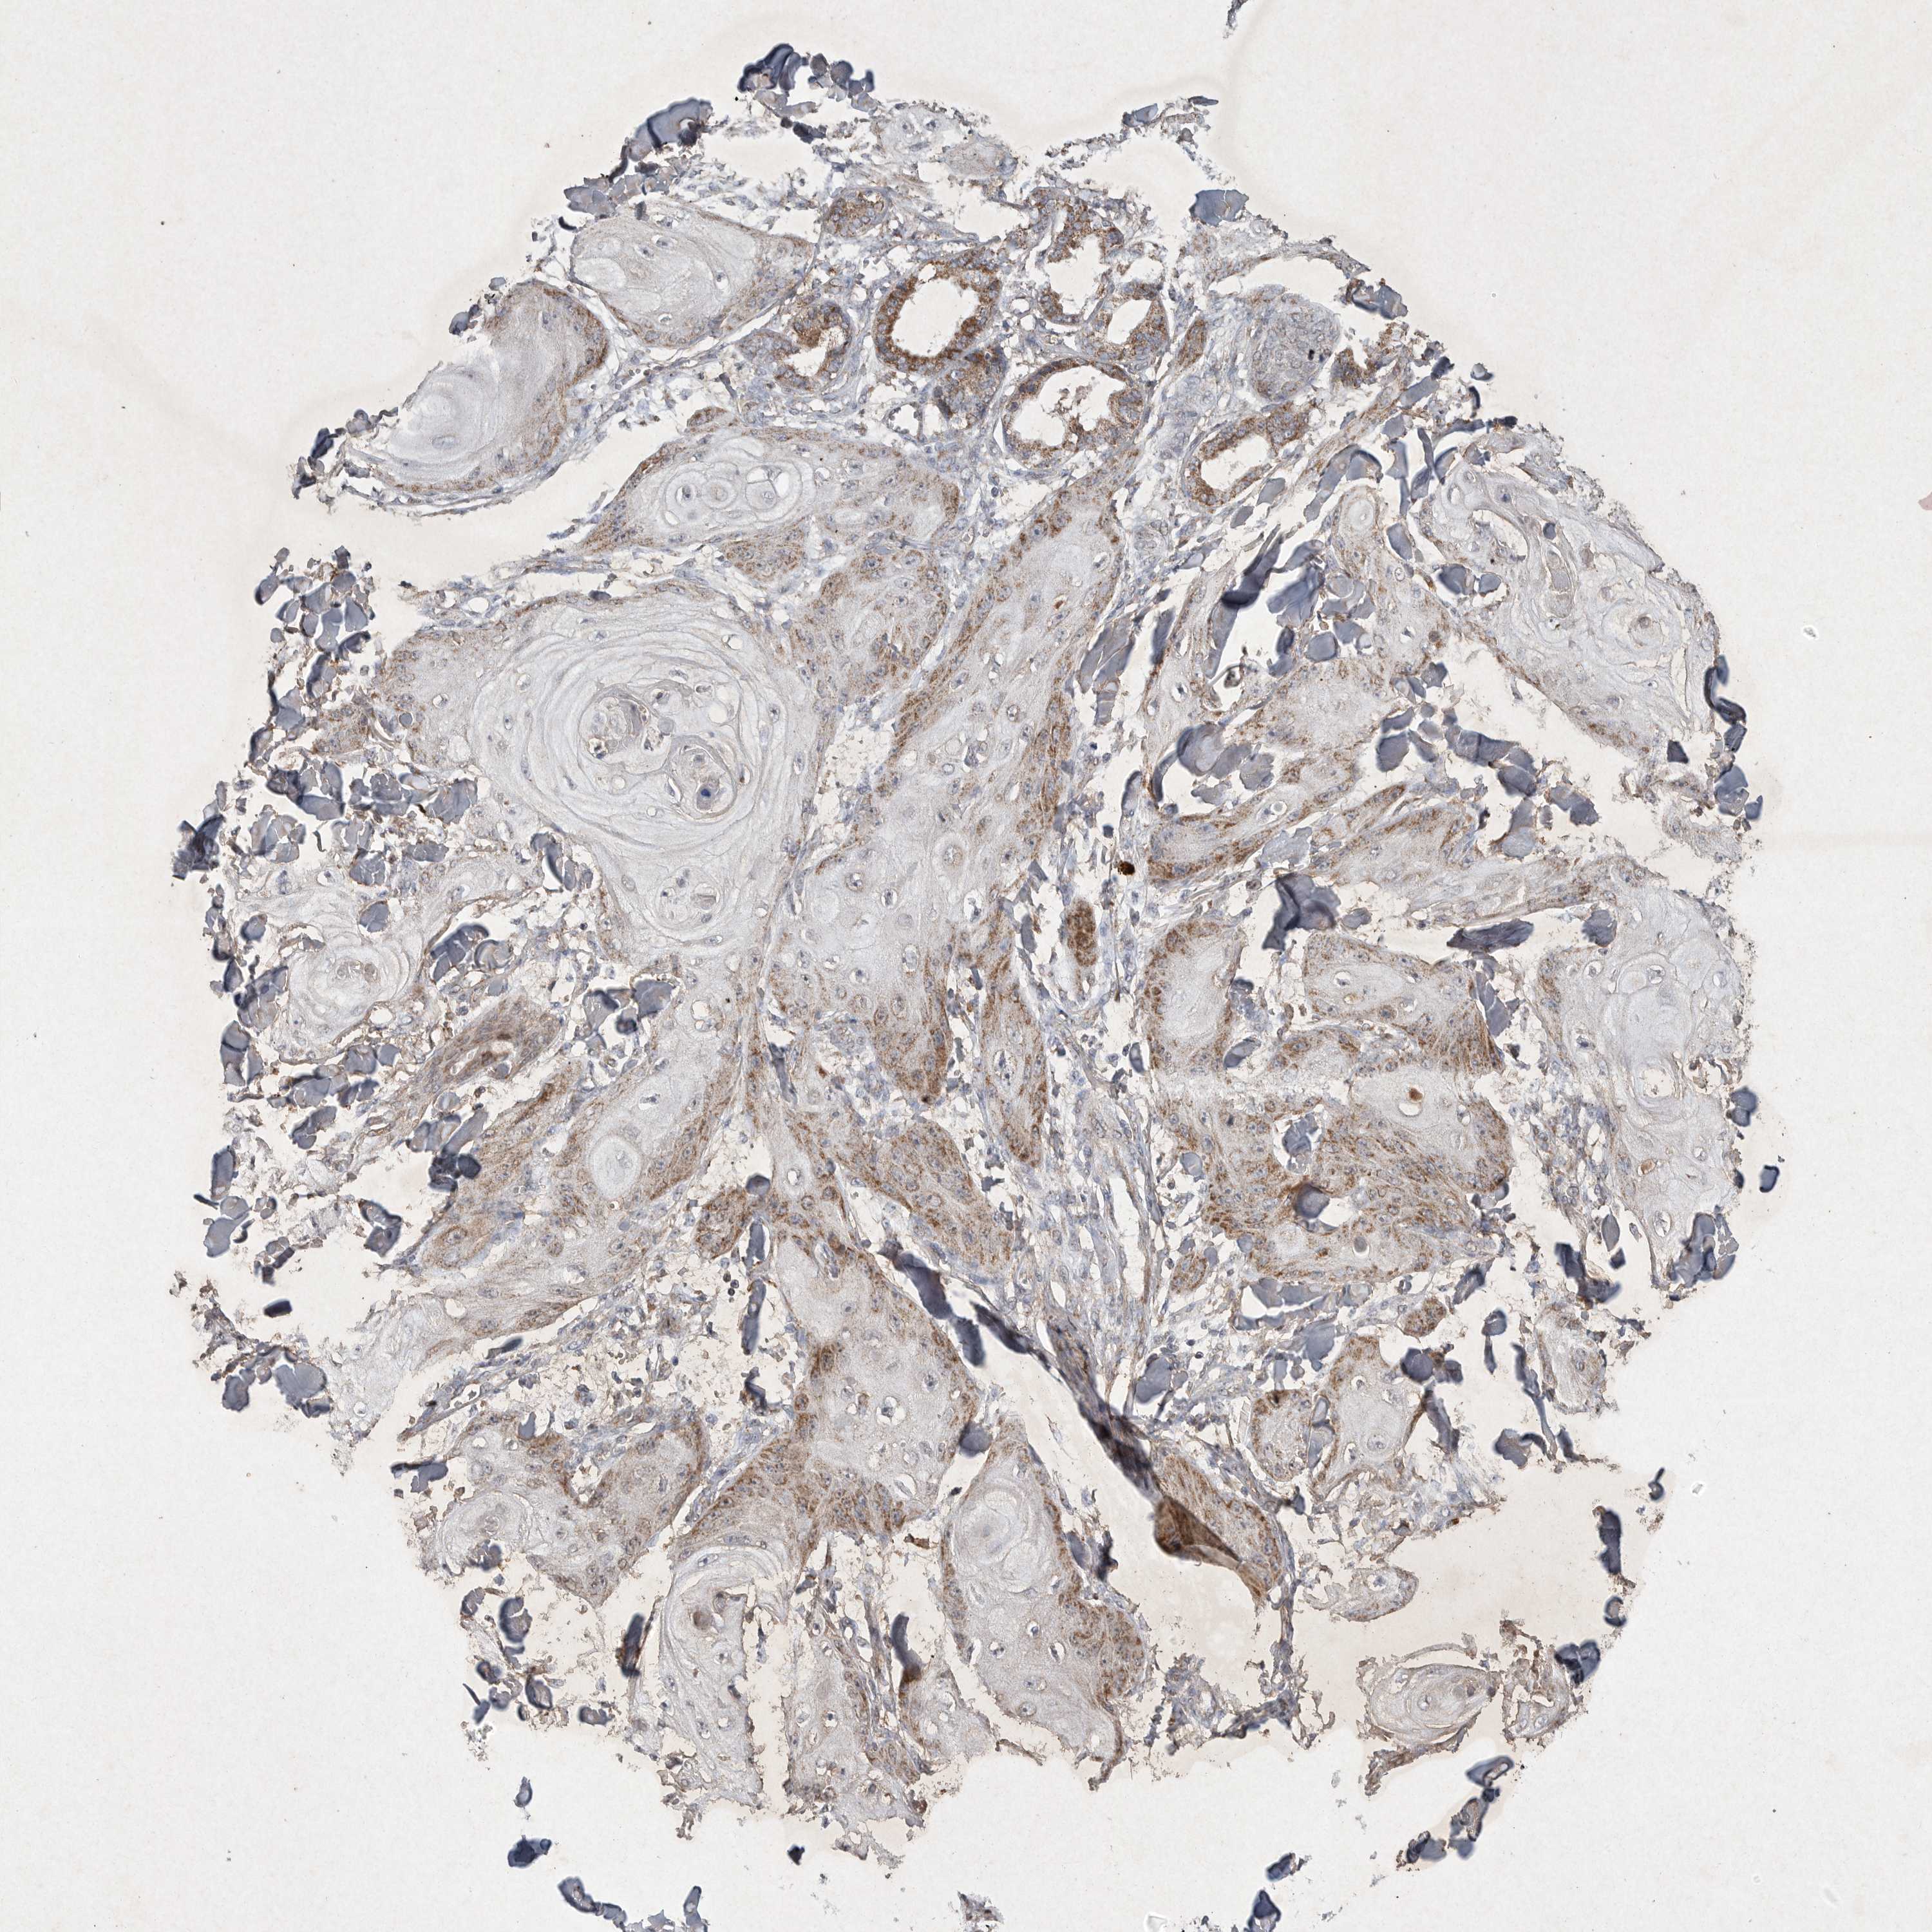

SKIN CANCER - Protein expressioni

A mouse-over function shows sample information and annotation data. Click on an image to view it in a full screen mode. Samples can be filtered based on level of antibody staining by selecting one or several of the following categories: high, medium, low and not detected. The assay and annotation is described here.

Antibody stainingi

Antibody staining in the annotated cell types in the current human tissue is reported as not detected, low, medium, or high, based on conventional immunohistochemistry profiling in selected tissues. This score is based on the combination of the staining intensity and fraction of stained cells.

Each image is clickable and will lead to virtual microscopy that enables deeper exploration of all samples and also displays staining intensity scores, fraction scores and subcellular localization as well as patient and tissue information for each sample.

Antibody CAB010162

Antibody CAB025656

Staining

High

Medium

Low

Not detected

Intensity

Strong

Moderate

Weak

Negative

Quantity

>75%

75%-25%

<25%

None

Location

Nuclear

Cytoplasmic/membranous

Cytoplasmic/membranous,nuclear

Squamous cell carcinoma, NOS

Basal cell carcinoma

Squamous cell carcinoma, metastatic, NOS